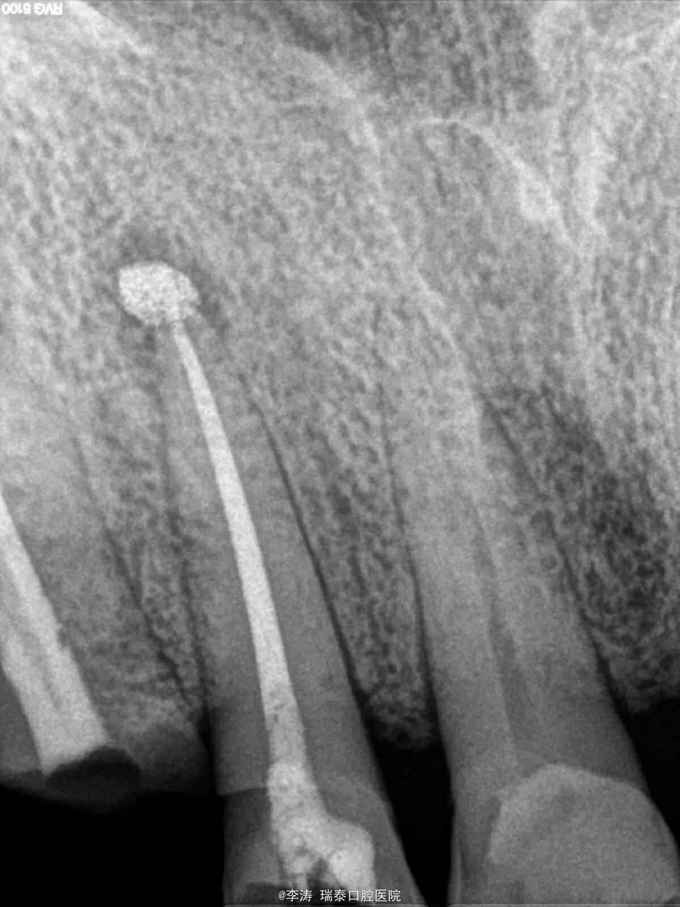

右上前牙疼痛不适1周,自诉半年前曾行根管治疗

13叩+,松-,x线片示13牙根尖暗影,根尖部有约1mm高密度影像,根管内充填影像

怀疑超充引起根尖炎症,建议行根管再治疗或者根尖切除术。患者选择先保守治疗,遂开髓。 术中根管内未见牙胶尖,大量vita糊剂充填于根管,遂行vita糊剂去除,拟行常规根管再治疗术。